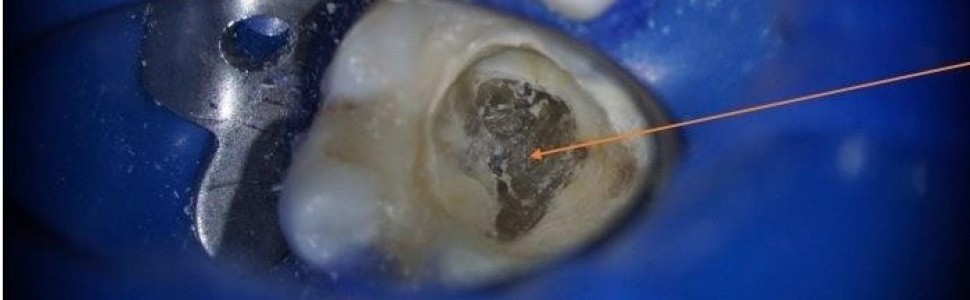

Leczenie kanałowe zęba trzonowego dolnego z zębiniakiem – opis przypadku

Zębiniaki, zwane również kamieniami zębowymi, mogą występować w każdej grupie zębów i u pacjentów w różnym wieku. Czynniki etiologiczne powstawania tego rodzaju obliteracji są różnorodne i nie do końca zdiagnozowane. Sama obecność zębiniaków nie jest wskazaniem do podjęcia działań inwazyjnych, ale w przypadku występowania objawów patologicznych konieczne jest opracowanie i wypełnienie kanałów. Leczenie endodontyczne stanowi wówczas wyzwanie nawet dla lekarzy specjalistów. W pracy przedstawiono opis przypadku leczenia kanałowego zęba trzonowego dolnego z dużym zębiniakiem. Leczenie zakończyło się sukcesem.

Pulp stones can occur in all groups of teeth and in patients of all ages. Their etiological factors are diverse and not fully diagnosed. Although the mere presence of pulp stones is not an indication for invasive measures, it is necessary to prepare and fill the canals when associated with pathological symptoms. In such cases, endodontic treatment can be challenge even for specialist doctors. The paper presents a case of root canal treatment of a lower molar with a large pulp stone. The treatment was successful.